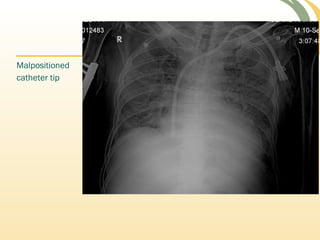

Malpositioned

catheter tip